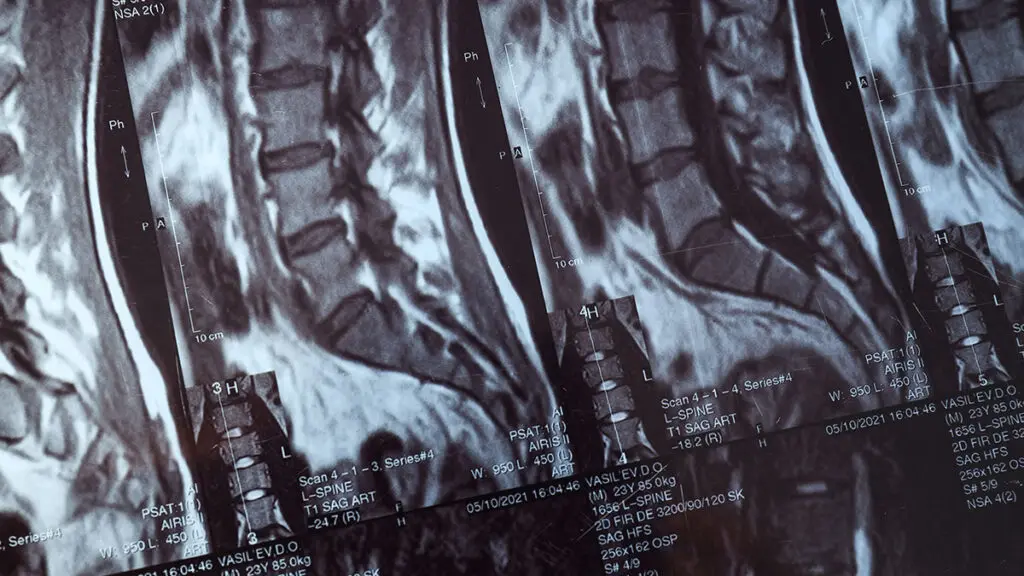

Global Spine Solutions offre a Roma approcci terapeutici avanzati e personalizzati per cura dolore cronico schiena, con un team multidisciplinare che integra neurochirurgia vertebrale, terapia del dolore, fisioterapia e medicina rigenerativa. Ogni percorso terapeutico viene costruito su misura sulla base della diagnosi clinica e strumentale, privilegiando le soluzioni mininvasive prima di considerare l'opzione chirurgica.

Il percorso per cura dolore cronico schiena disponibile presso Global Spine Solutions comprende: terapie farmacologiche mirate, infiltrazioni guidate (epidurali, periradicolari, faccette), radiofrequenza, nucleoplastica, terapie rigenerative (PRP, acido jaluronico) e programmi di fisioterapia post-procedurale. Il paziente viene seguito dall'inizio alla fine del trattamento con follow-up clinici periodici per monitorare i progressi.